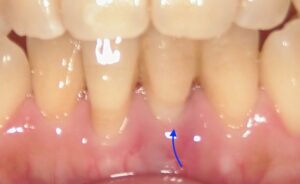

画像の矢印の歯が歯周病が進行し暫間固定で経過を見ていました。

周囲のホ根が完全になくなってしまいましたので

抜歯をし、その歯を接着剤でとめました。

矢印がその歯になります。

内側から見た状態です。実際歯があるように

見えます。